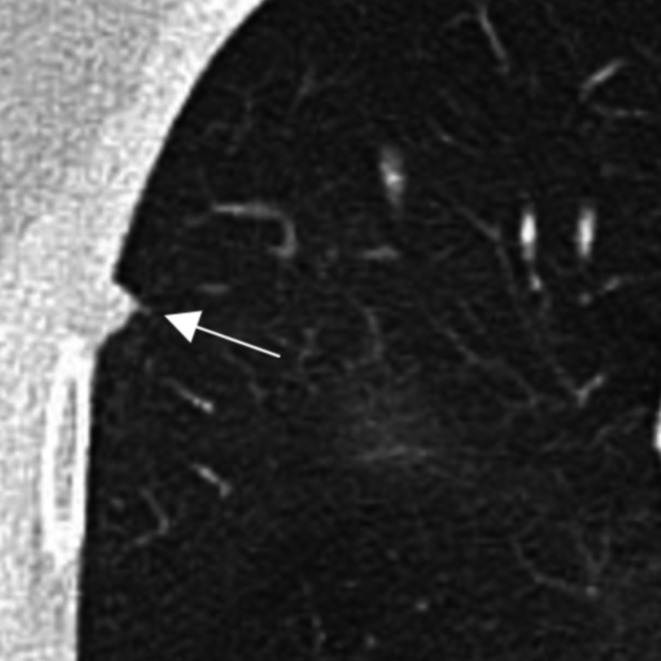

越来越多的肺癌筛查项目的采用和成像技术的进步显著增加了肺结节的检测,无论是偶然的还是通过筛查。本文件为临床医生提供了一个全面的指南,以解决管理不确定肺结节(ipn)的复杂性,强调以人为本和多学科的护理。ipn根据大小和形态进行分类,并有恶性肿瘤风险分层、诊断评估和随访的具体指南。专门的肺结节评估小组(LNETs)和结节多学科会议(MDMs)在确保指南遵守、简化诊断途径、减少不必要的调查和改善结果方面发挥着关键作用。结构化IPN项目在早期肺癌检测、改善早期肺癌检测和减少治疗启动延迟方面已经证明了益处。有效的管理策略包括使用标准化的报告模板,利用经过验证的风险模型,如PanCan恶性肿瘤风险模型和议定的ipn后续协议。本文档强调了获取先前成像以评估生长和计算计算机断层扫描(CT)扫描之间的技术差异的重要性。任何被认为正在生长的结节都需要在结节MDM上进行讨论,并决定酌情进行组织活检。基于结节特征和风险概况,结节MDM有助于优化最安全、最有效的活检技术。通过整合多学科专业知识和坚持以证据为基础的协议,服务可以改善ipn的及时诊断和管理,最大限度地减少过度调查,减少过度诊断的机会,并最终提高患者的预后和肺癌生存率。

The increasing adoption of lung cancer screening programs and advancements in imaging technologies has significantly increased the detection of pulmonary nodules, both incidentally and through screening. This document provides a comprehensive guide for clinicians to address the complexities of managing indeterminate pulmonary nodules (IPNs), emphasising person-centred and multidisciplinary care. IPNs are categorised based on size and morphology, with specific guidelines for malignancy risk stratification, diagnostic evaluation, and follow-up. Dedicated lung nodule evaluation teams (LNETs) and nodule multidisciplinary meetings (MDMs) play a critical role in ensuring guideline adherence, streamlining the diagnostic pathway, reducing unnecessary investigations, and improving outcomes. Structured IPN programs have demonstrated benefits in early lung cancer detection, improved detection of early-stage lung cancer, and reduced delays to treatment initiation. Effective management strategies include use of standardised reporting templates, utilising validated risk models such as the PanCan malignancy risk model and agreed protocols for follow up of IPNs. This document highlights the importance of accessing prior imaging to assess for growth and accounting for technical differences between computed tomography (CT) scans. Any nodule considered to be growing requires discussion at a nodule MDM with decision to act for tissue biopsy as appropriate. A nodule MDM will assist in optimising the safest and most efficient biopsy techniques based on nodule characteristics and risk profile. By integrating multidisciplinary expertise and adhering to evidence-based protocols, services can improve the timely diagnosis and management of IPNs, minimise over-investigation, reduce chance of overdiagnosis and ultimately enhance patient outcomes and lung cancer survival.